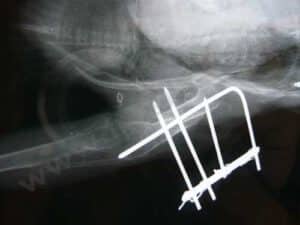

En conséquence : si votre vétérinaire traitant est ouvert, c’est bien évidemment l’interlocuteur privilégié. Si vous ne pouvez pas vous déplacer, un vétérinaire à domicile connaissant les oiseaux peut apporter les premiers soins. En son absence, pour ce type d’urgence, une consultation sans délai dans un service d’urgence est indispensable. Il faudra faire des radiographies, des soins locaux importants (le plus souvent sous anesthésie générale), adapter le traitement de la douleur à l’évolution de la situation, lutter contre l’état de choc par une réanimation médicale, …

Pratiquement toujours nécessaire. Selon la situation, une radiographie est nécessaire Cependant l’urgence principale est de gérer l’état de choc et la douleur associée. Il est important de garder l’animal au chaud et de le réalimenter. Une fois l’animal stabilisé, une éventuelle intervention chirurgicale peut être envisagée.